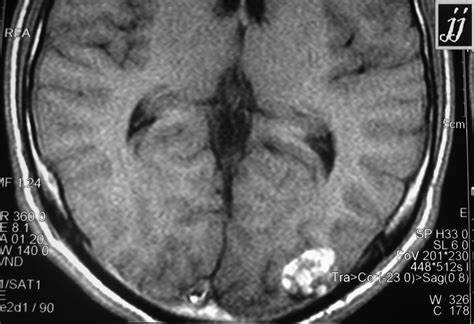

脑海绵状血管瘤(CMs)是一种血管畸形,由薄的透明血管通道组成,没有脑实质的介入。这些病变周围有含铁血黄素沉积和胶质细胞边缘,可能是血栓形成了其位置是可变的,70%-80%的颅内CMs起源于幕上。

随着磁共振成像技术的日益普及,CM的诊断率也有了很大的提高。事实上,在磁共振成像之前,CMs并不常见,其评估和处理仅在病例报告和小型临床系列中描述。这些血管病变在诊断性血管造影中并不明显,因为它们的性质是低压系统,因此被称为血管造影隐匿性血管畸形。然而,影像学的好转不仅增加了对症状性病变的诊断,而且偶然发现了CMs,其中40%是偶然发现的。与CMs相关的不同风险是出血或微出血的发生,这些出血或微出血可导致死亡、神经功能缺损、癫痫,或者可能根本没有临床缺陷。